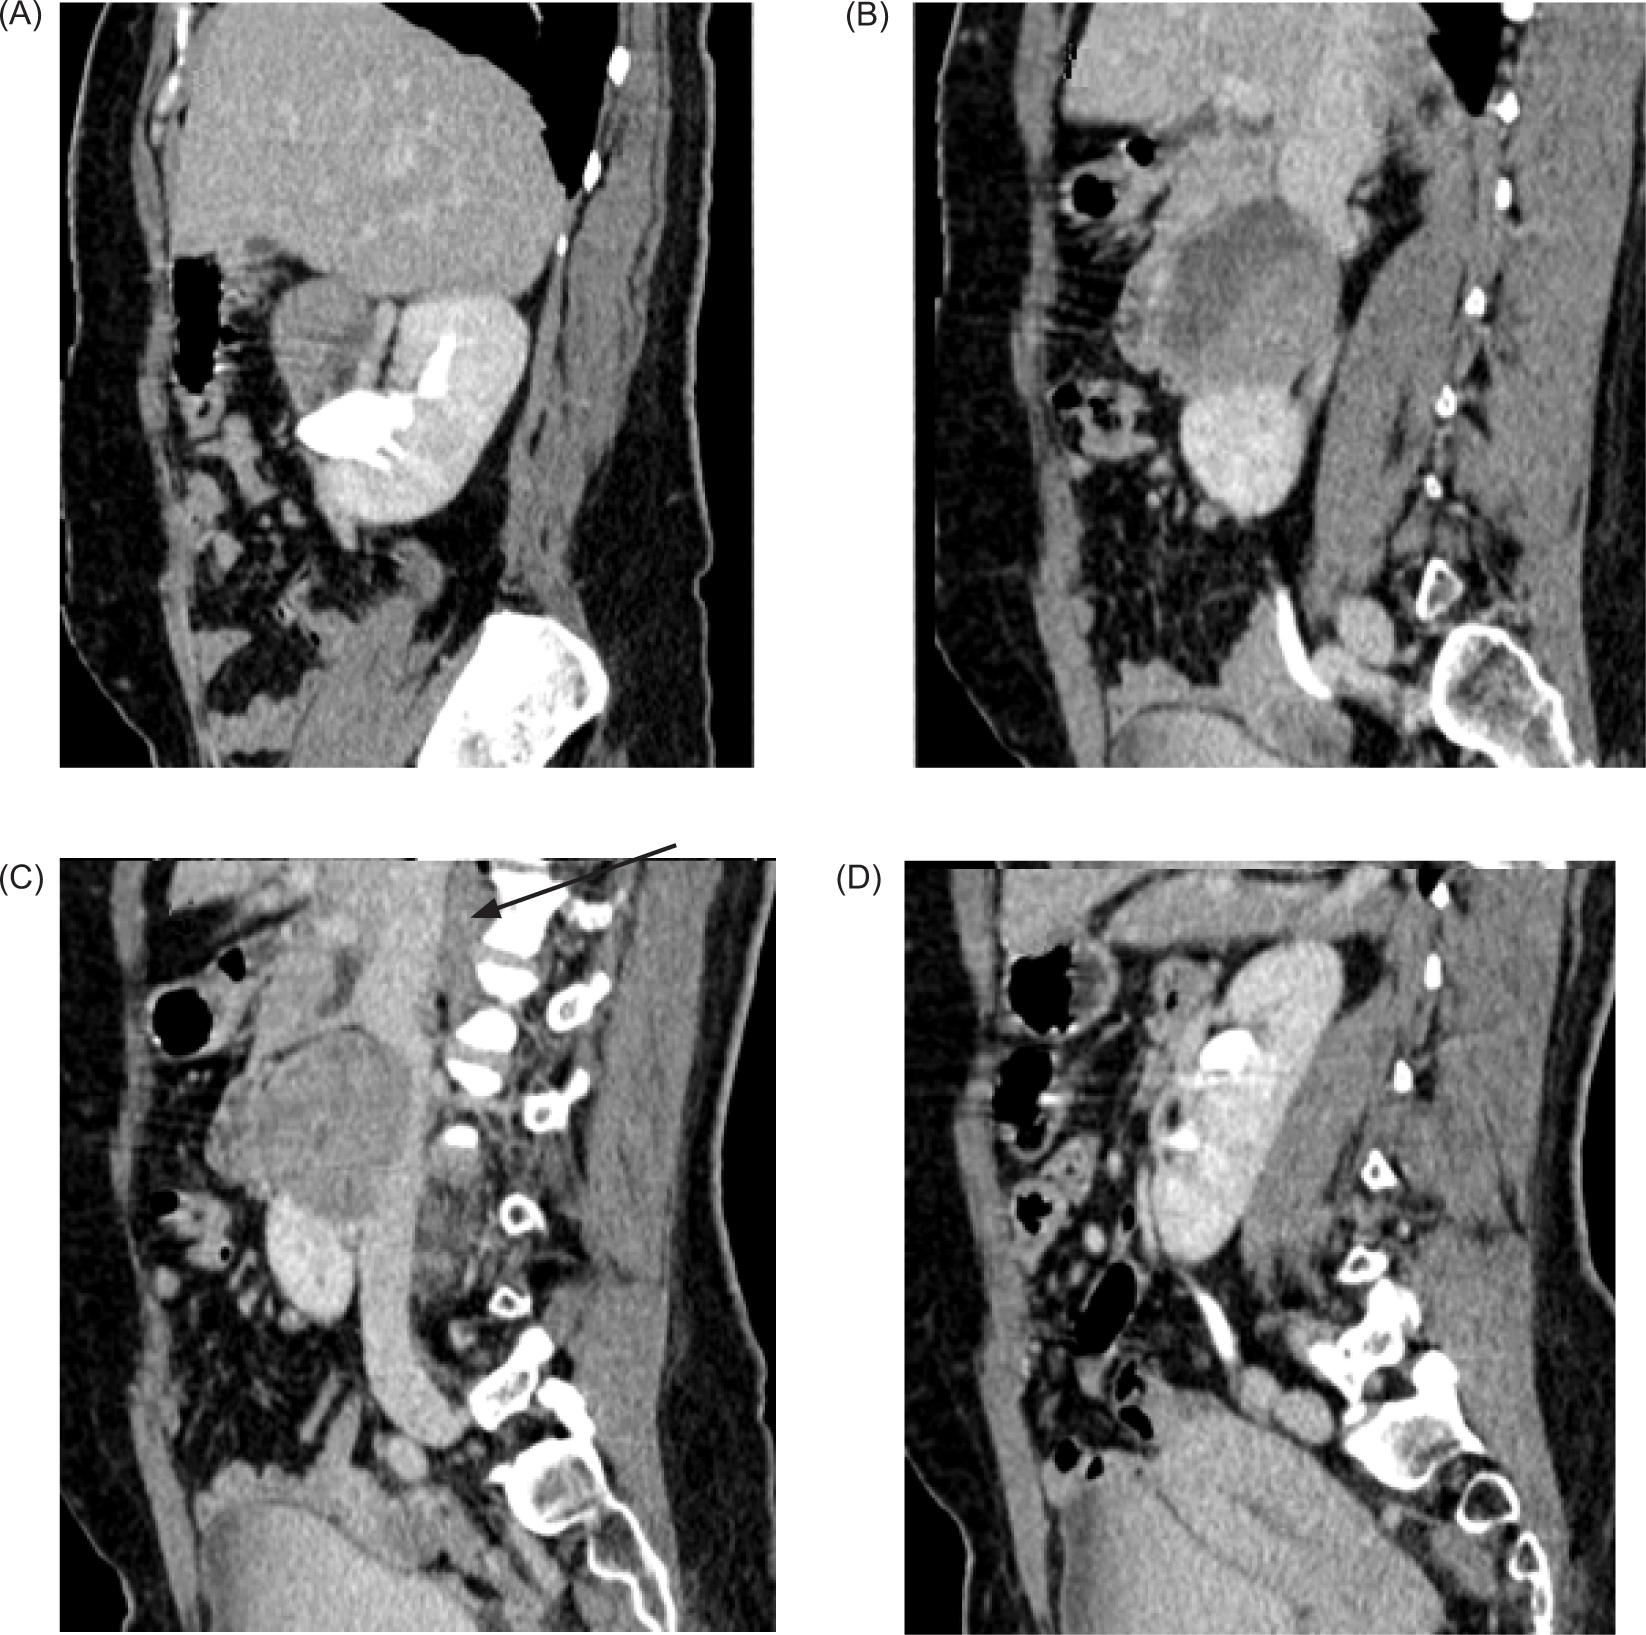

The pancreatic head was compressed and displaced anteriorly; posteriorly mass effect was noted on anterior surface of inferior vena cava with obliteration of intervening fat plane. IVC as a result was compressed and flattened anteroposteriorly (Figure 4).

Figure 4: (A–D) Contrast enhanced CT sagittal images—Mass arising from the isthmus, posteriorly compressing the IVC with obliteration of intervening fat planes (arrow).

On the right side, the mass was extending anterior to the right renal hilum and abutting anterossuperior surface of right renal pelvis.